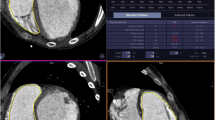

Reproducibility

For both methods inter- and intra-observer agreement was high in all measurements, as illustrated by high ICCs with small limits of agreement (Table 3; Fig. 2). For both methods, RVEDV, RVESV and RV mass showed significant differences between repeated measurements. However, mean differences were small and considered not clinically relevant. In Fig. 2, Bland–Altman plots show interobserver variability for RVESV, RVEDV and RVEF for both methods. For RVEDV, RVESV and RV mass the limits of agreement were narrower when trabeculae and papillary muscles were excluded from the RV blood volume (method 2). The ACintra/inter of all measurements was not statistically significantly different for RVEDV, RVESV and RVEF (p > 0.1). Method 2 had a significantly better ACinter than method 1 for RV mass measurement, with a median (IQR) ACinter of respectively 94.1 (92.1–97.1) % and 77.2 (72.1–82.6) %.